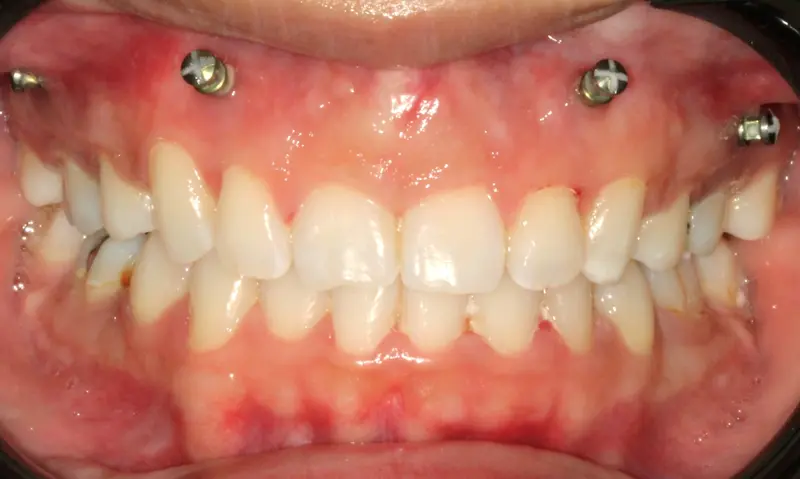

The Diagnosis

Deep bite with over-erupted upper central incisors. The patient presented with a "Gummy Smile" and uneven gingival margins, where the front teeth sat too low relative to the upper lip.

The Engineering

We utilized Temporary Anchorage Devices (TADs) to apply pure intrusive forces. By anchoring to the bone, we lifted the anterior teeth and gum line upwards (Intrusion) to reduce the gummy display and level the smile arc without jaw surgery.

After treatment: Vertical Control & Intrusion

After